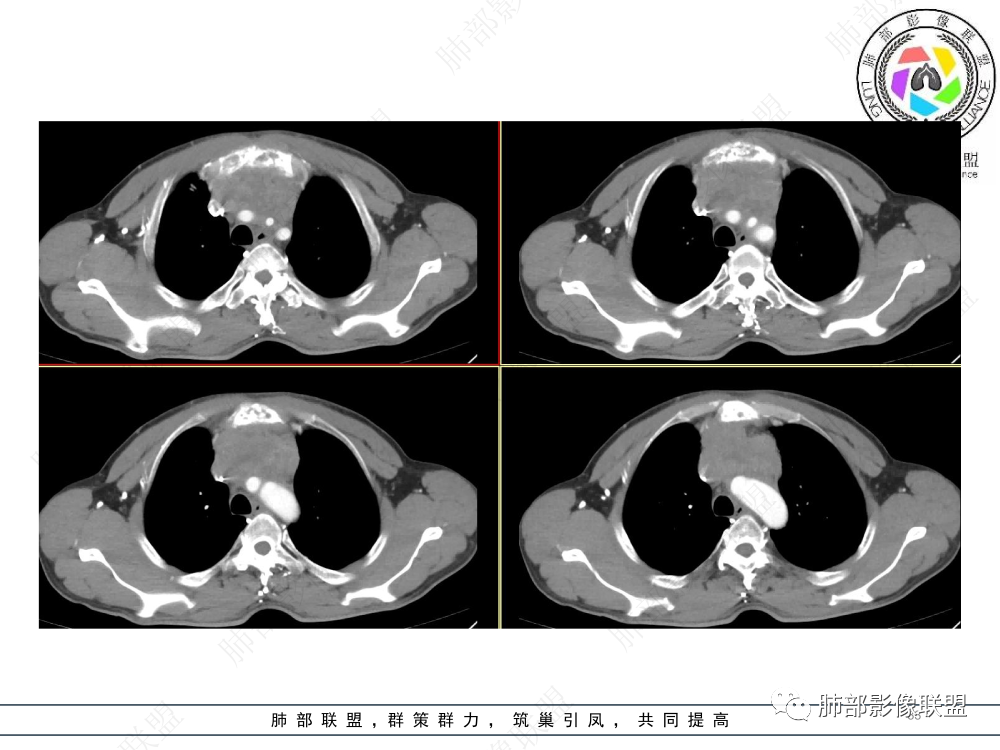

1.临床资料:中老年男性,病史较长-8个月,主诉胸痛,实验室资料:乳酸脱氢酶(LDH)升高。

2.影像表现:前上纵隔较大肿块,密度不均,形态不规则,边界不清,有结节样突起,脂肪间隙显示不清。病灶侵犯左无名静脉及上腔静脉,其中左无名静脉闭塞(胸背部侧支循环明显,亦表明回流受阻)。增强后轻中度不均强化。坏死边界欠清晰。可见心包积液,提示心包受侵犯。右侧上叶及纵隔胸膜下结节影,疑胸膜肺转移可能。胸骨柄后缘皮质不完整,疑骨质破坏(未提供骨窗及矢状位图像)。左锁骨上可见肿大淋巴结。